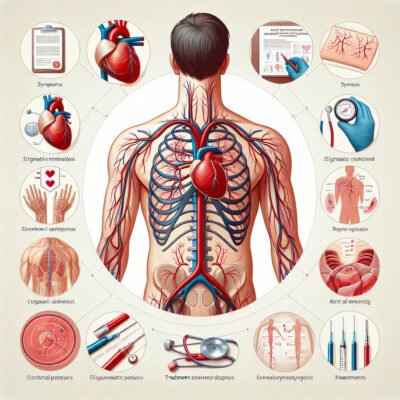

Встановити діагноз SVBA – це своєрідний квест для лікаря. Він потребує всього: від комп’ютерної томографії до ендоскопії. Але як розпізнати? Вірний діагноз – це половина справи.

Не кожен лікар задумується про SVBA. Але коли є підозра – це виклик. Іноді знімки й дослідження не одразу дають відповідь. Тут доводиться бути наполегливими.

Гарною новиною є те, що SVBA можна лікувати. Шляхи різноманітні: від консервативної терапії до хірургічного втручання. Але кожен шлях – особливий, все залежить від специфіки випадку.

Іноді хірургія – єдиний вихід. Звільнити артерію від стискання – завдання не з легких, проте можливе. Сучасні методи дозволяють забезпечити ефективний результат.

Україна може забезпечити високоякісне лікування SVBA. Медичні заклади, оснащені сучасним обладнанням, здатні надати необхідну допомогу. І наші лікарі не поступаються світовим стандартам.